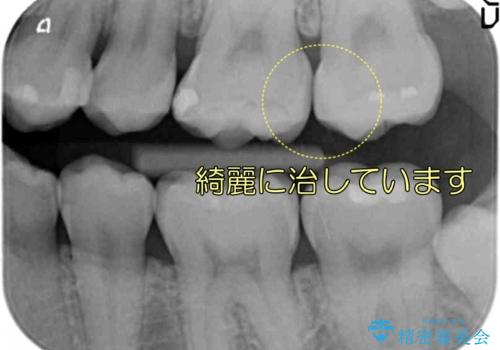

そこで、部分矯正を行い、歯の間を広げてしっかりした歯型を取りました。

広げた期間は2週間ほどです。

広げた後は歯が接するように修復するため、物が詰まることはありません。